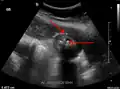

Abdominal ultrasonography showing gallstones, wall thickening and fluid around the gall bladder -

Acute cholecystitis as seen on ultrasound. The closed arrow points to gallbladder wall thickening. Open arrow points to stones in the GB -